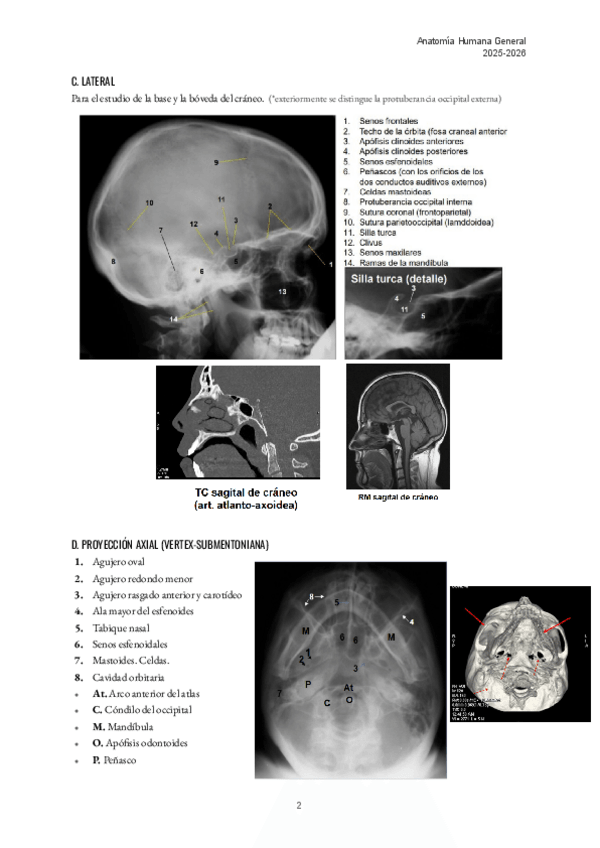

He publicado nuevos apuntes de 1º Anatomía Humana General: TEMA-34.-ANATOMIA-RADIOLOGICA-SIMPLE-DEL-CRANEO.pdf

3 páginas